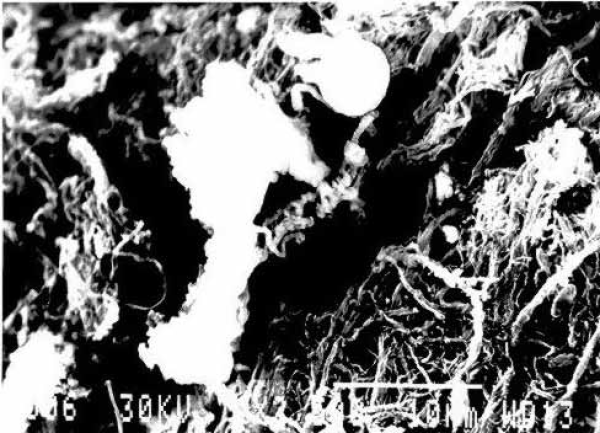

Elektronska mikroskopija dna ulceroznog kratera karotidnog arteriosklerotičnog plaka. Aktivirani trombociti adheriraju na ogoljena fibrozna, kolagena i elestična vlakna ekstracelularnog matriksa.